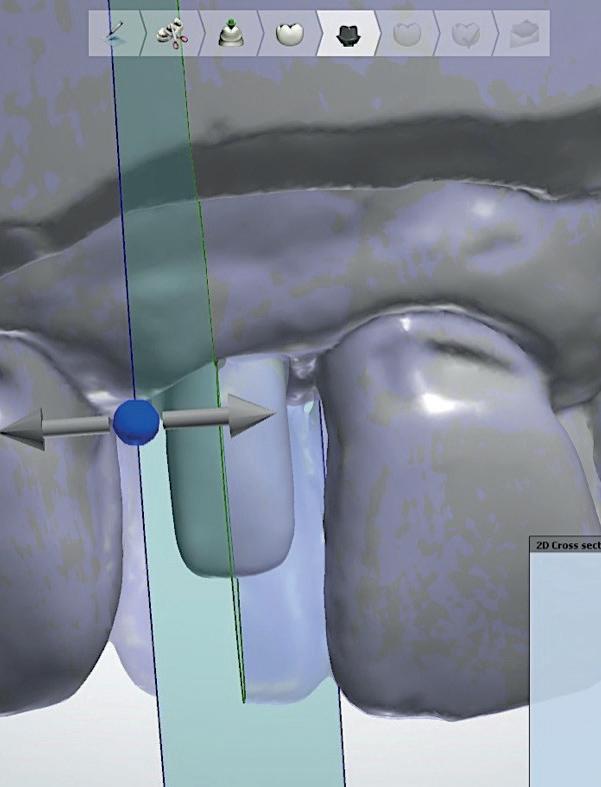

Digitale planning en directe plaatsing

In het huidige tijdperk zijn we vooral bezig met topdown planning, waarbij wij het eindresultaat simuleren en de bijbehorende behandeling met CAD/ CAM-technieken voorbereiden. De implantaten worden “dwingend” geplaatst door een tevoren gemaakte mal, waarbij het soms al mogelijk is meteen een tijdelijke of zelfs “definitieve” voorziening te plaatsen (afbeelding 15).

4: Horizontale doorsnede CBCT met radiolucentie mesiopalatinaal van de 11

de patiënt zich zorgen maakt over deze toevalsbevinding, wil hij de 11 laten beoordelen door een endodontoloog.

Er wordt een CBCT gemaakt die een laesie aan de mesiopalatinale zijde van 11 laat zien (afbeelding 4).

Aangezien dit zou kunnen duiden op een crack of fractuur, wordt besloten om het element te openen en te inspecteren.